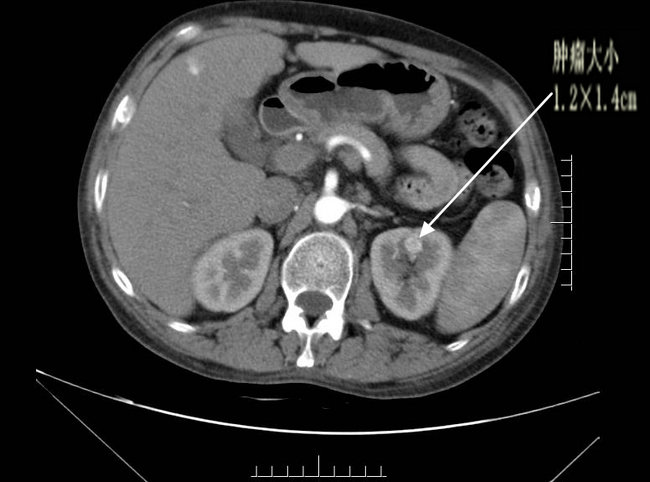

▲ 术前SCT、超声影像检查结果

由于肿瘤较小(1.2*1.4cm),位于左肾肾门处,被血管包围,位置隐蔽,常规超声检查很难发现。超声诊断科主任杨青教授及其精英团队术前反复检查,模拟术中精确定位。术中督导,精确定位,给手术提供动态精准的三D指导,保证了左肾小肿瘤的外科精准切除,术后检查标本肿瘤完整,与术前CT、超声检查符合,术后病理报告:(左)肾透明细胞癌,Fuhrman 1-2级,肿瘤包膜完整,切缘未见癌波及。